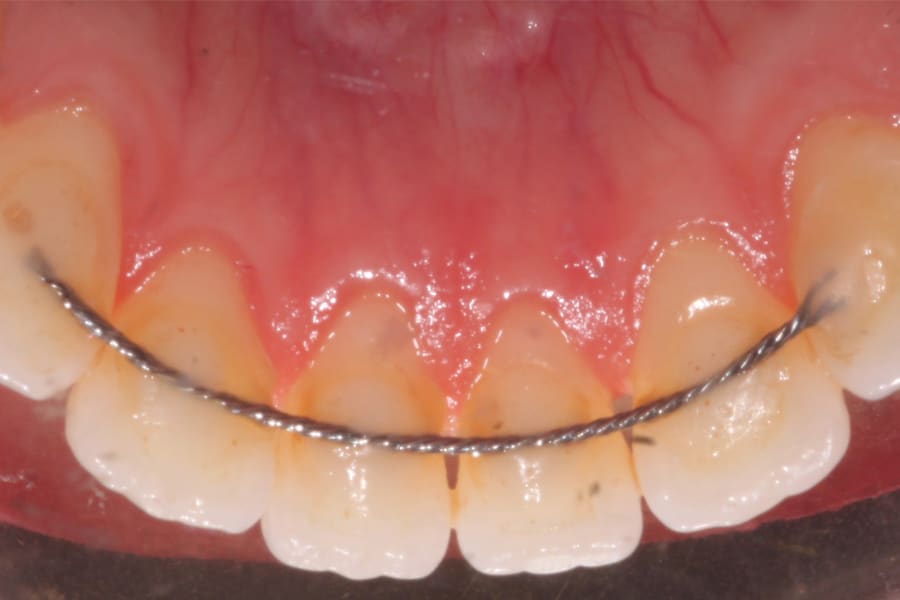

A popular example of this approach is the twisted stainless-steel wire retainer (Figure 1). This design features ease of fabrication and placement as well as minimal cost. Frequently, a twisted lingual retainer can be fabricated chairside and placed immediately with no preparation, impressioning, or laboratory fabrication required. Consequently, this design is commonly utilized. It can be made from a very thin wire (such as a .009" ligature tie) that is folded over and spun down (or twisted) then formed to the arch curvature and direct bonded. Annealing the formed wire prior to placement can be beneficial, as this can remove the "memory" that stainless steel possesses if not permanently deformed.

Obviously, more suitable and reliable fixed lingual retention designs are needed, and, fortunately, many are available. As described above, the twisted chairside fabricated design can be unreliable. A well-suited alternative is a passive braided design as shown in Figure 2 (Ortho FlexTech® stainless steel, Reliance Orthodontics, relianceorthodontics.com). The braided design does not uncoil over time. The lingual retainer is placed in passive fashion after being cut to the proper length from a spool and bonded to the appropriate teeth. This relatively inexpensive alternative is fabricated chairside with no laboratory intervention or special preparation required. One potential downside is that it is a relatively bulky option.